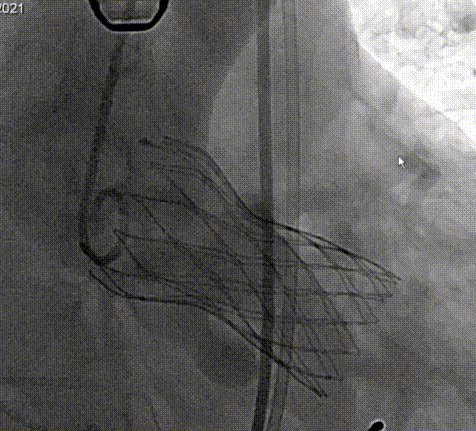

为保证瓣膜的植入的效果,选择AV23瓣膜,在LAO 6° CRA 29°角度下释。释放高度推荐标准位(瓣环下2-4mm)。释放后可调整至右前斜足位进一步确定人工瓣膜形态。

TaurusOne顺利过弓

TaurusOne标准位释放

术后造影

对本例手术,罗建方教授团队通过术前详尽的检查分析评估,对可能发生的各种突发情况进行充分预估,并准备了相应的应对预案,手术中采用左右重叠体位,标准位释放,术后跨瓣压差降至0mmHg,血流动力学得到有效改善,为患者带来更长久的生存预期和更高的生活质量。本例手术的成功开展再次展现了罗建方教授团队在诊治高难度复杂主动脉瓣膜疾病的雄厚实力和丰富经验,也为临床上心室腔小、心肌肥厚、横位心的Type1型二叶瓣患者行TAVR治疗提供了更多的参考。